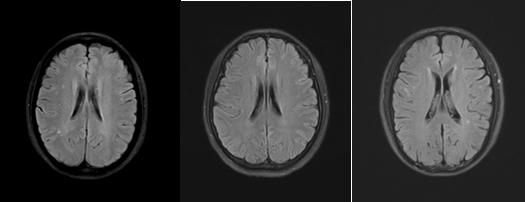

髓腔脱失的原因有很多,包括先天代谢性和后获得性。先天代谢性脱髓鞘主要指的是脑白质营养不良,以儿童青少年起病居多,这类疾病脱髓鞘在影像上多呈广泛对称性。后天性获得性脱髓鞘的病因又有很多种,包括缺血、炎症、感染、代谢、中毒、外伤等。更多见的是由高血压、糖尿病、高血脂等导致的微小血管病变引起缺血,继而导致髓鞘的脱失,也就是我们最常见的缺血性脱髓鞘,其本质是脑梗塞。这些脱髓鞘往往是个慢性的过程,一般没有临床症状,只有在做颅脑核磁检查时才被发现;病灶个头通常较小,数量上有时个别几个,有时候也可以有不少,呈点灶状或小片状分布在皮层下或者深部脑白质或者侧脑室前后角旁。看专科医生时,如果判断属于这种类型的脱髓鞘,就需要对上述相关的危险因素进行筛查、监测和管理,并完善颈部血管超声、经颅多普勒、颅内血管核磁等检查,看看大中血管的情况,如果没有比较大的斑块,没有明确的血管狭窄。就要管理危险因素(血压、血糖、血脂、吸烟过量饮酒等)并每半年到一年复查一下就行了。

(FLAIR序列及T2WI序列显示缺血性脱髓鞘病变)

还有一部分人有上述特点病灶,但是没有筛查到上述危险因素,往往给大家带来困扰,到底是啥原因导致的呢?其实在我们小时候都会多次接种疫苗甚至长大还会接种或加强一些疫苗,如狂犬疫苗、乙肝疫苗,有的冬天还会接种流感疫苗;还有就是类似感冒的病毒感染,从小到大估计每个人都会经历无数次。实际上接种疫苗或者感冒后脑子里就可能出现几个甚至多个病灶,从本质上讲它们是炎性脱髓鞘病灶,只是人体轻的、限制性的一个免疫反应和结果。这种脱髓鞘病灶也绝大多数是幼时留下来的,被后来体检或者其他原因做颅脑核磁时所发现。如看专科医生,判断属于此种情况,就不必担心了。因为这些病灶一是无症状性的,二是这些病灶长期稳定存在,如果是第一次做核磁发现,那么第二、三年再复查比较一下,如果较前没有增多和变化,就基本不需要管它们了。这里提醒大家不要过于纠结,希望这些病灶能够消失,因为它们是陈旧性病变,不会消失而会稳定一直存在;但是它们既没有症状,未来也不会变成活动性病灶,所以请大家不要担心。

(常见无症状炎性脱髓鞘病变)